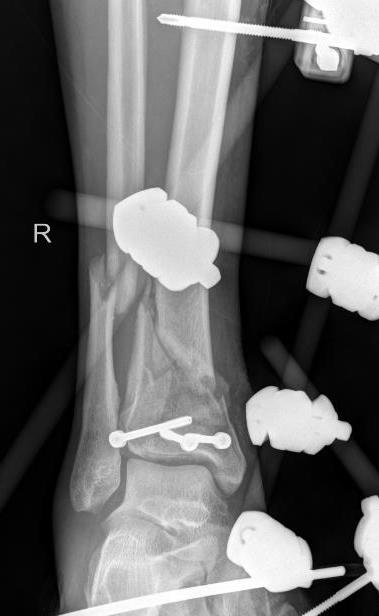

ORIF with Plates

Principle

Restore articular surface

Fix articular surface to metaphysis

Consider fibula ORIF

- holds fracture out to length

- via posterolateral incision

- need wide skin bridge from anterior incision

- must avoid malreduction

Anatomical reduction joint surface

Attach metaphysis to diaphysis

- anatomically contoured low profile locking plates

- anterolateral L shaped plate via anterior wound

- small incisions proximally to insert screws

- 8 cortices above fracture

- small medial incision to insert medial plate percutaneously / MIPO techniques